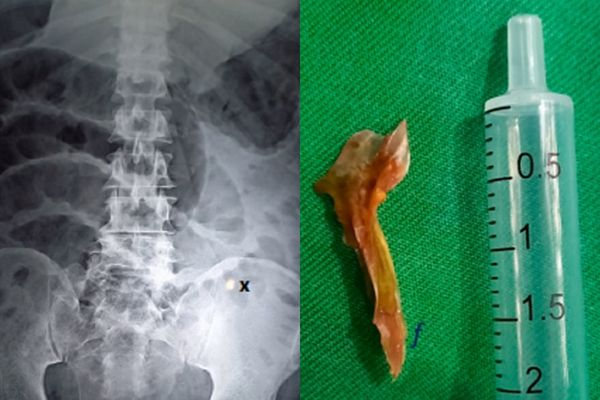

外科医生马上为男子进行开刀手术,发现男子的肠子里竟然有一根约2公分长的鱼刺,而且还穿破了小肠约0.5公分,才会导致肠道被感染。

医生为男子切除了约10公分的肠道,男子的情形依旧没有好转,8小时后因心脏骤停而宣告不治。